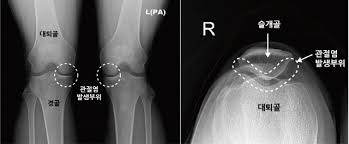

관절염

관절염은 무릎 구부릴 때 통증의 가장 흔한 원인 중 하나입니다. 나이가 들면서 무릎 관절의 연골이 마모되고, 이는 통증과 염증을 유발합니다. 관절염은 퇴행성 변화로 인해 발생하는 경우가 많으며, 일반적으로 노인에게서 더 많이 나타납니다. 관절염으로 인한 통증은 구부릴 때 더욱 심하게 느껴질 수 있으며, 이는 일상적인 활동에 큰 지장을 줄 수 있습니다.

- X-레이: 뼈의 구조와 손상 여부를 확인하기 위해 X-레이 촬영이 필요할 수 있습니다.